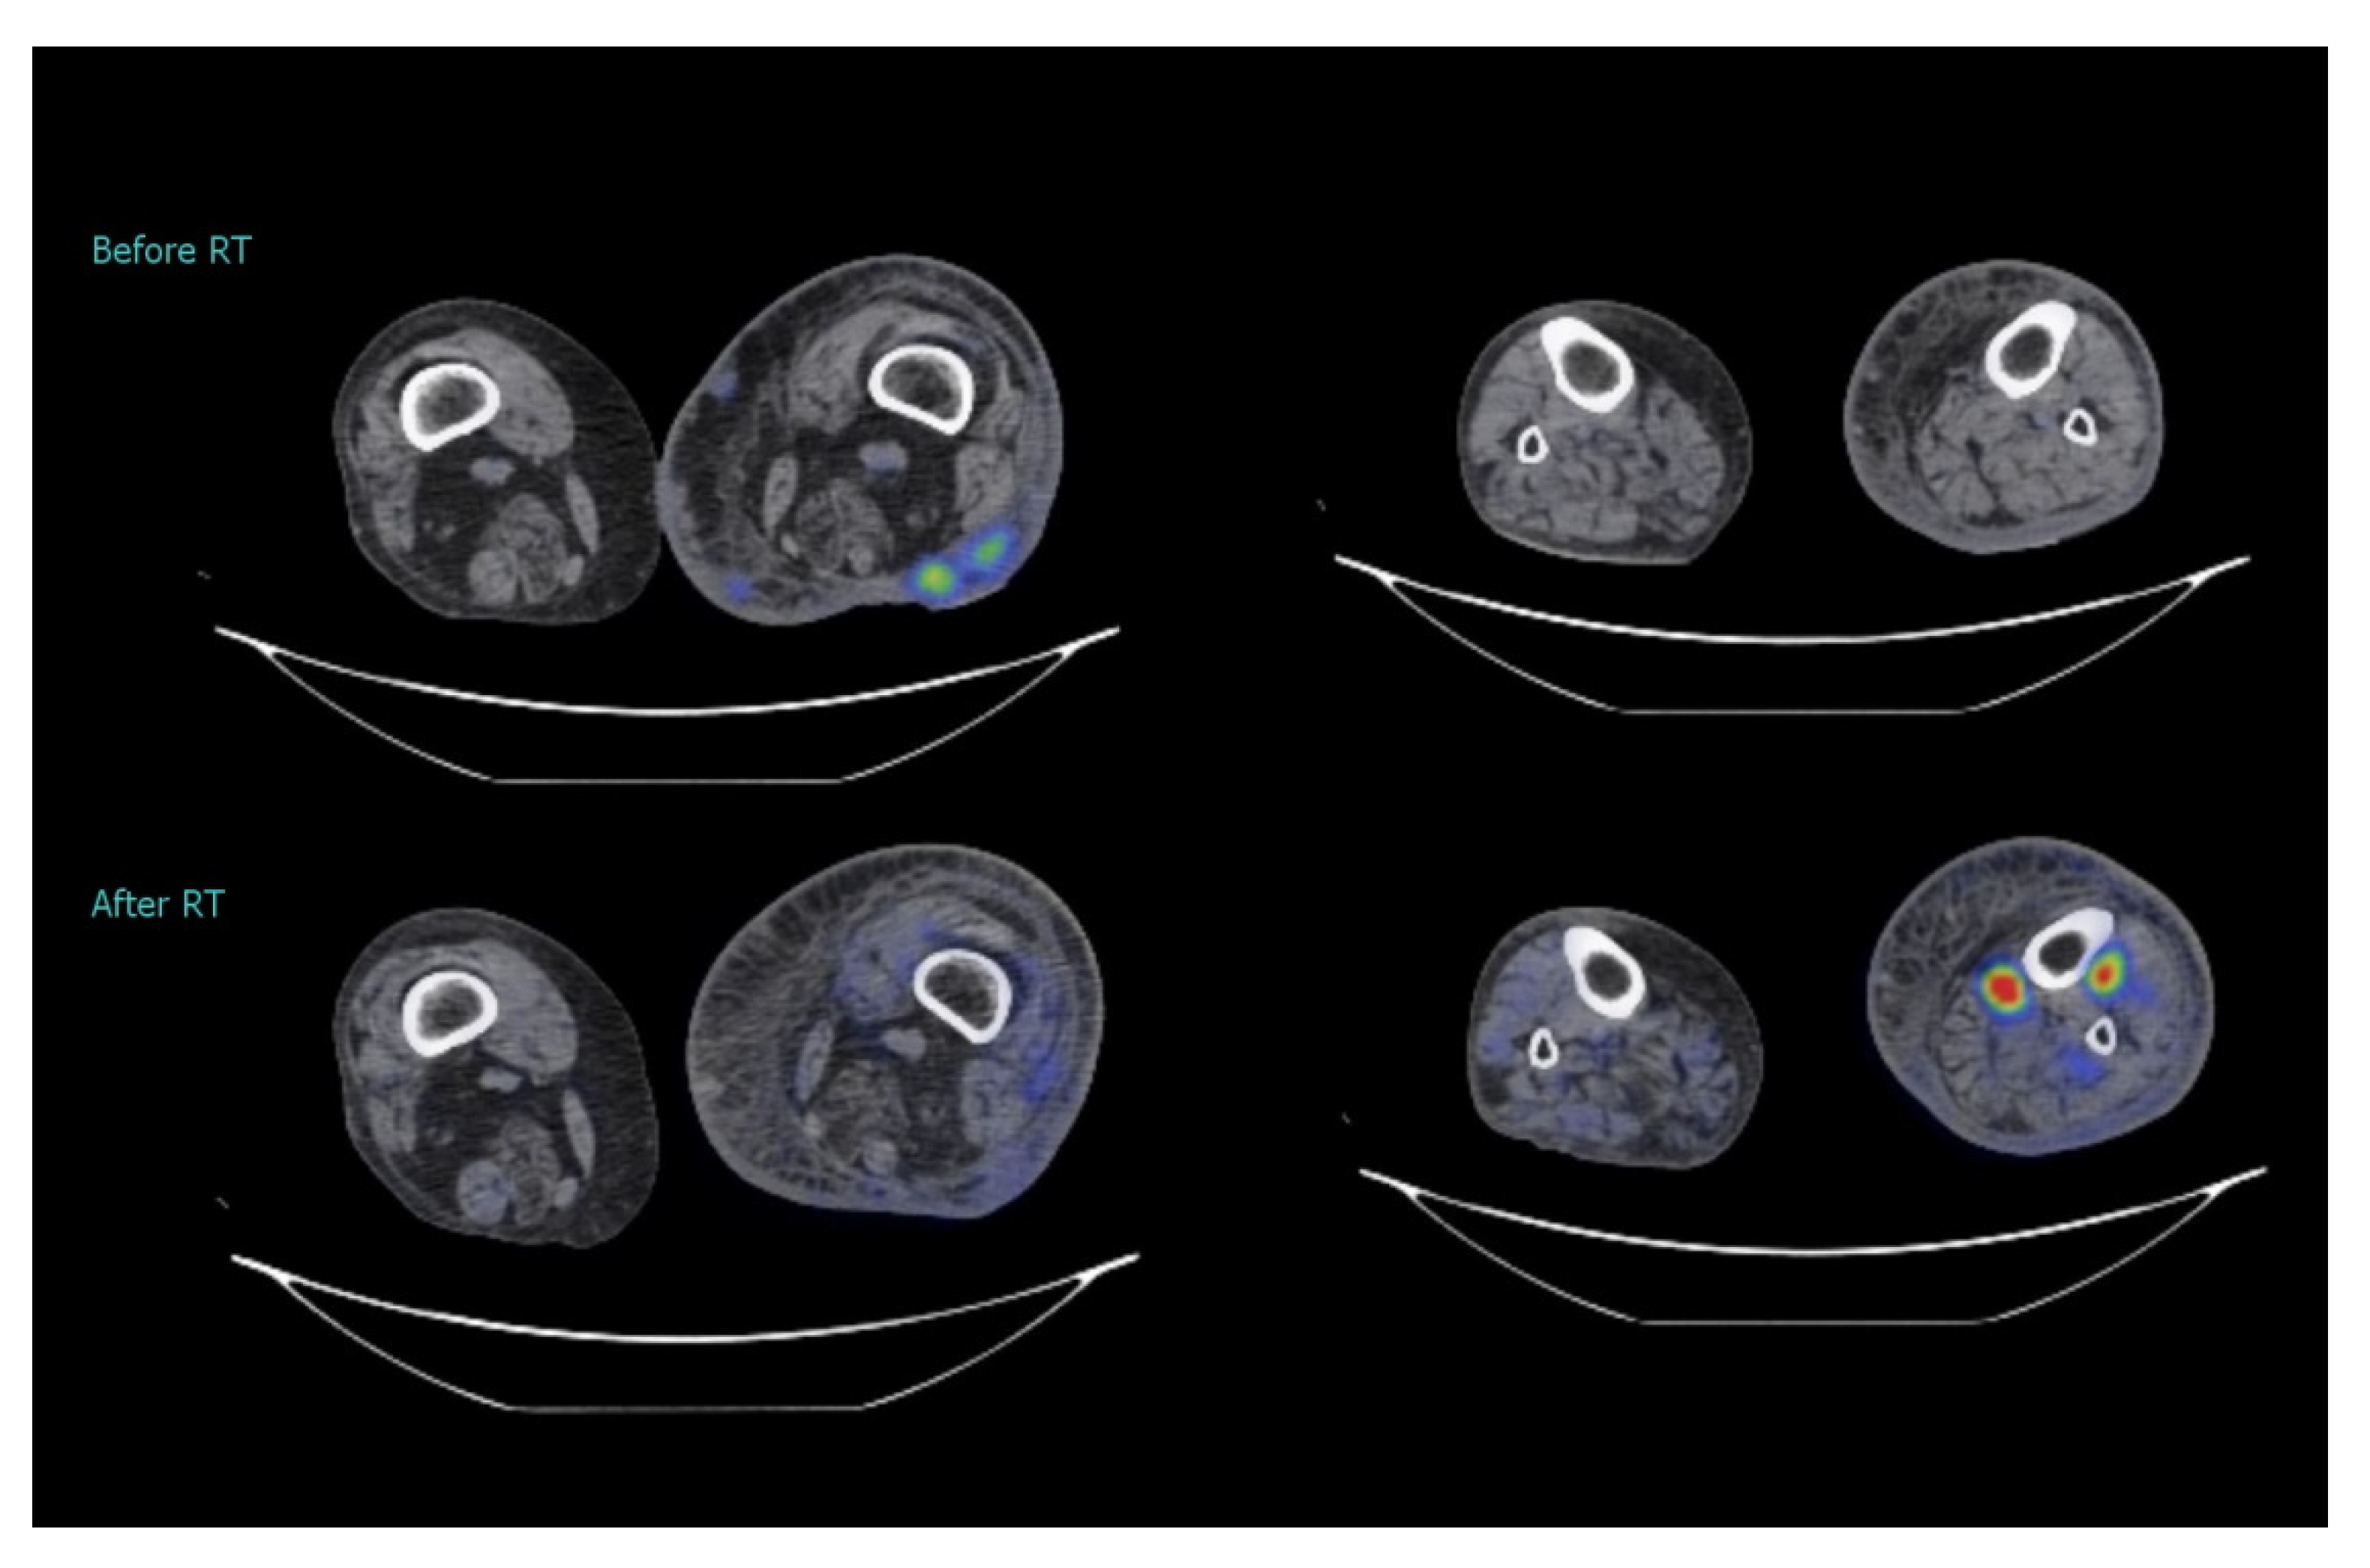

2. Case Study